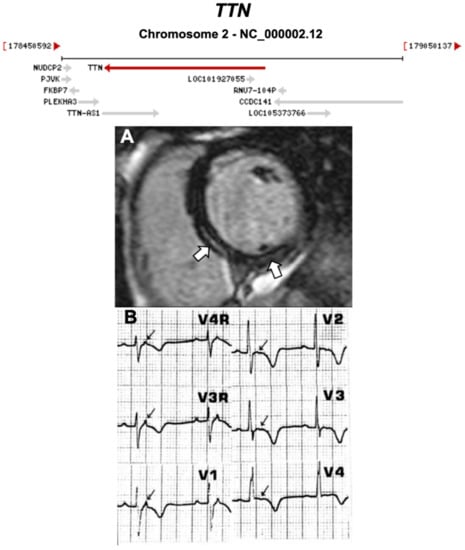

3.2.1. Titin (TTN) (Encoded by TTN)

- Taylor, M.; Graw, S.; Sinagra, G.; Barnes, C.; Slavov, D.; Brun, F.; Pinamonti, B.; Salcedo, E.E.; Sauer, W.; Pyxaras, S.; et al. Genetic variation in titin in arrhythmogenic right ventricular cardiomyopathy-overlap syndromes. Circulation 2011, 124, 876–885. [Google Scholar] [CrossRef] [PubMed]

- Brun, F.; Barnes, C.V.; Sinagra, G.; Slavov, D.; Barbati, G.; Zhu, X.; Graw, S.L.; Spezzacatene, A.; Pinamonti, B.; Merlo, M.; et al. Titin and desmosomal genes in the natural history of arrhythmogenic right ventricular cardiomyopathy. J. Med. Genet. 2014, 51, 669–676. [Google Scholar] [CrossRef]

| TTN | Sarcomere | 18% | AD | RV, LV, BIV | - | 2q31.2; 365 | DCM | Limited for ARVC |